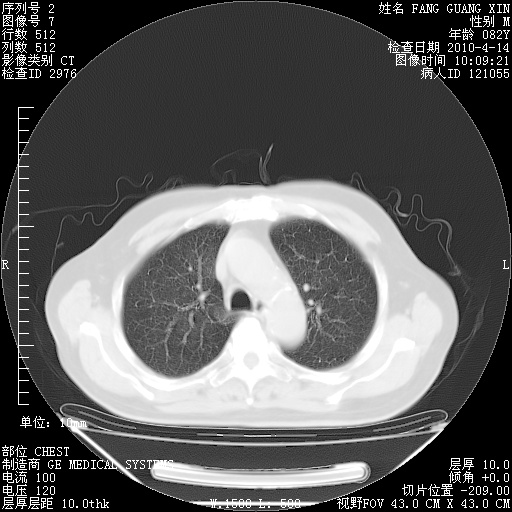

4月14日肺部CT

27.JPG

28.JPG

29.JPG

30.JPG